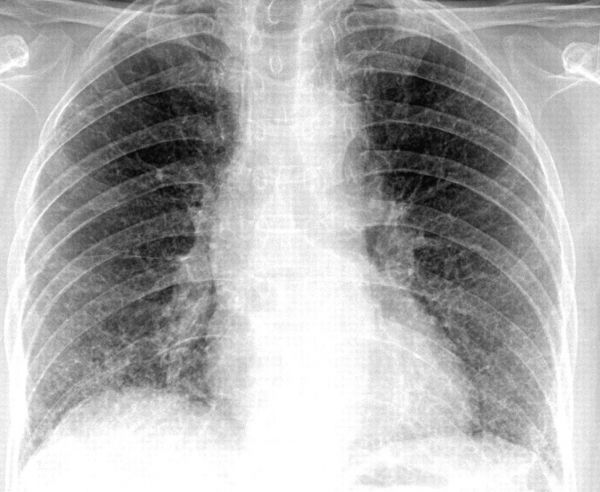

Viêm phổi kẽ trên phim CT scaner

Bệnh nhân bị bệnh phổi kẽ có thể thấy các triệu chứng như sau: cảm giác khó thở, đặc biệt là trong hoặc sau khi lao động hay hoạt động thể lực vừa và nặng; ho khan. Bài viết này sẽ nói rõ hơn về hội chứng Viêm phổi kẽ trên phim CT scaner. Mời các bạn tham khảo!